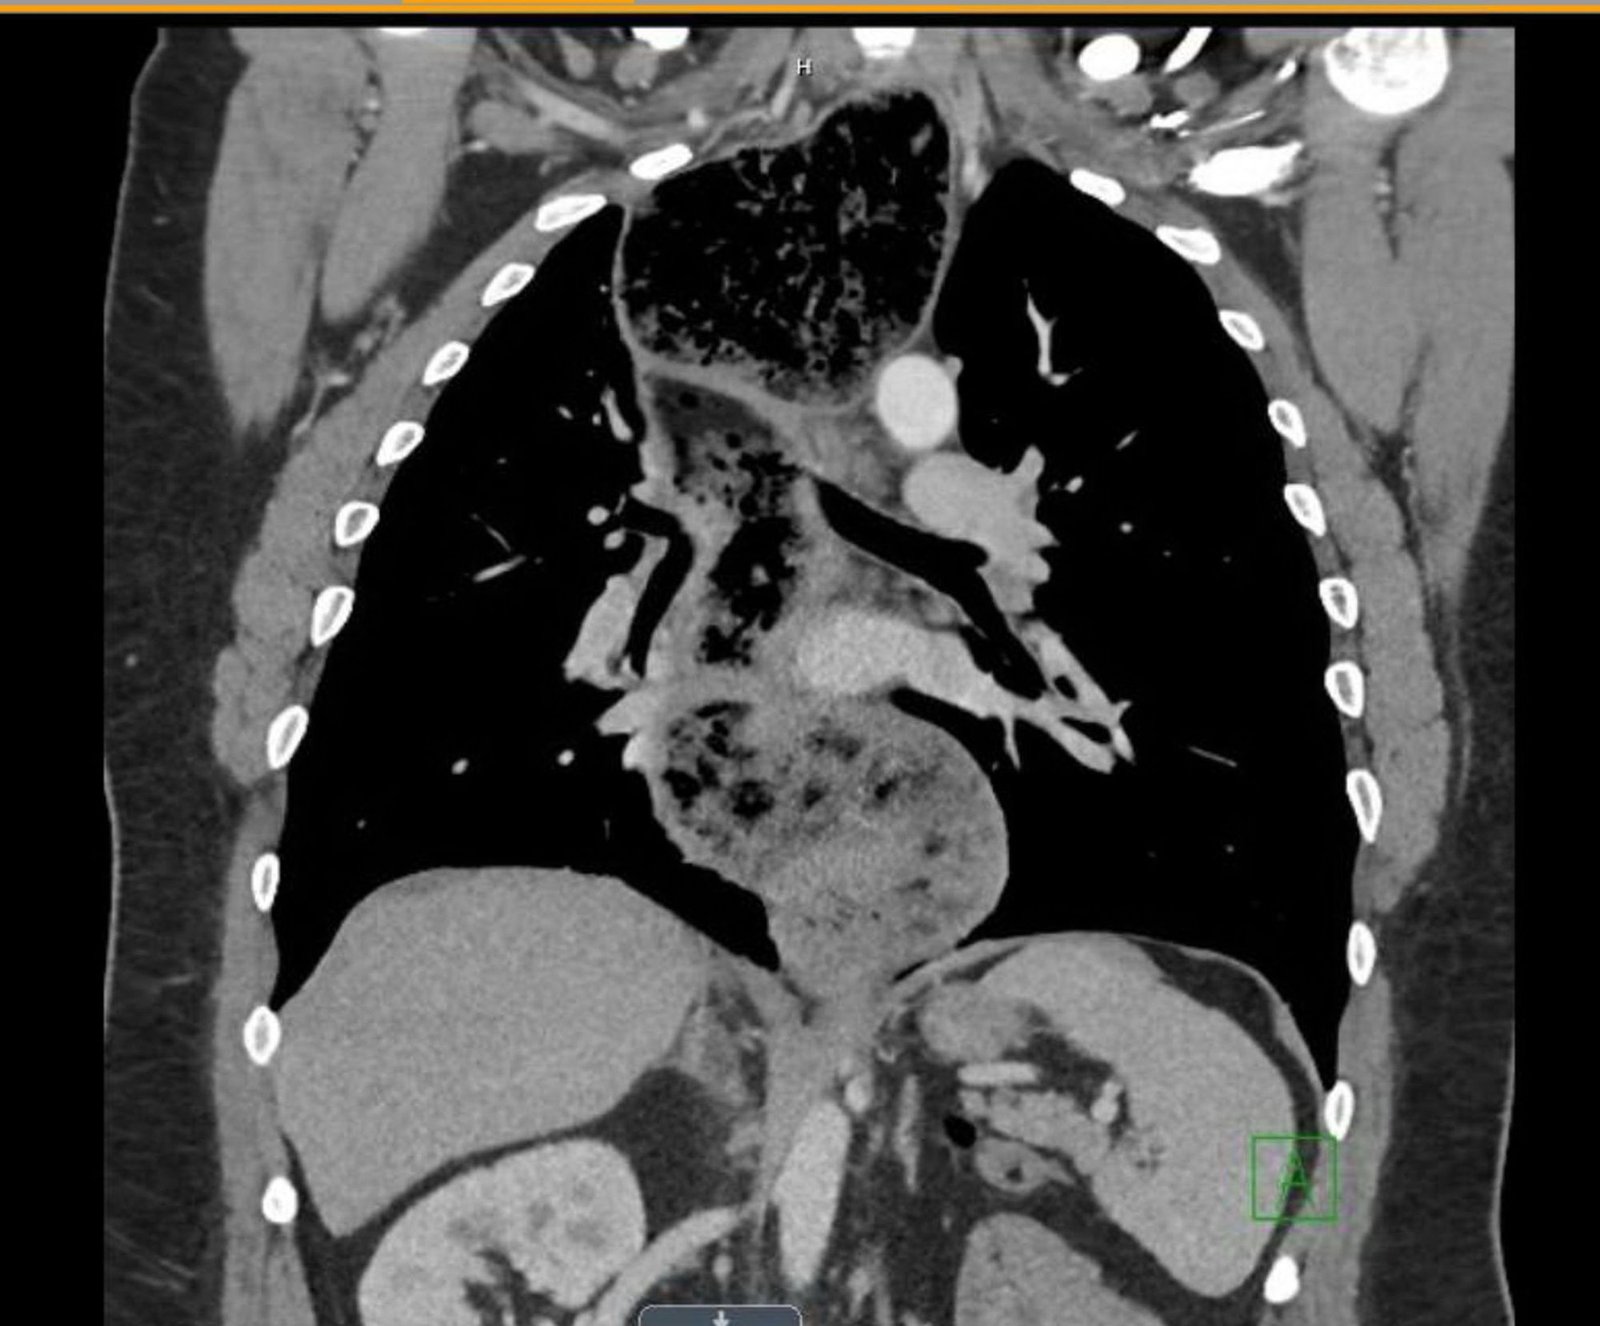

The chest X-ray demonstrated a markedly widened mediastinum (red brackets), raising concern for thoracic aortic aneurysm/aortic dissection, which prompted labs and contrast-enhanced computed tomography (CT) of the chest. The CT revealed a dilated proximal esophagus that narrowed distally (yellow tracing and red arrow), with particulate material, mass-effect on the trachea (purple outline), and bilateral patchy opacities suggesting aspiration. Barium esophagram showed a drastically dilated esophagus filled with contrast (yellow arrow), terminating into the classic “bird’s beak sign” (red arrow) at the lower esophageal sphincter (LES). Esophageal manometry later confirmed achalasia, proving that widened mediastina can have unexpected etiologies.